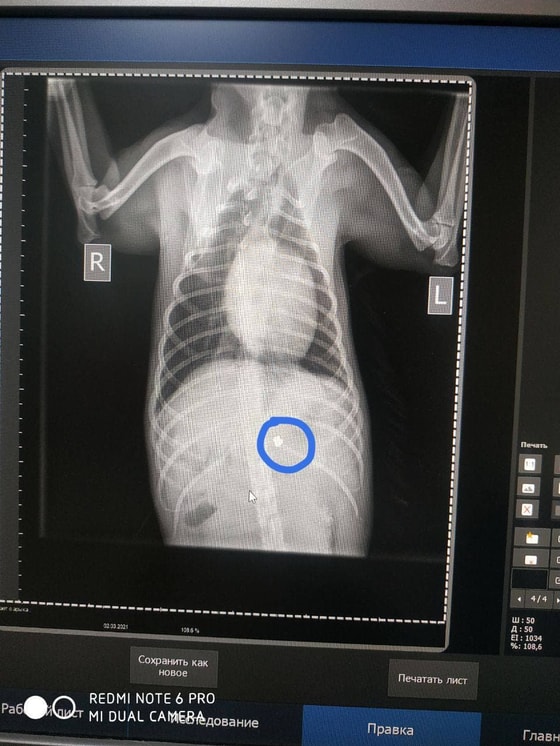

Пуля находится в тканях собаки.

Джахонгир не только согласился дождаться транспорт, но и попытался накормить собаку колбасой, купленной в магазине неподалёку. Раненое животное было доставлено в клинику «Доктор Вет». К этому моменту, состояние собаки резко ухудшилось. На основании рентгеновского снимка врачами было установлено, что в животное стреляли из оружия. К сожалению, пуля находится в тканях собаки. В данное время, ей проводится курс интенсивной терапии,

– сообщили в Mehr va Oqibat.